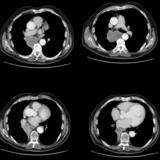

Mass  RLL collapse 5 CT

Date: 03/02/2006

Views: 4057